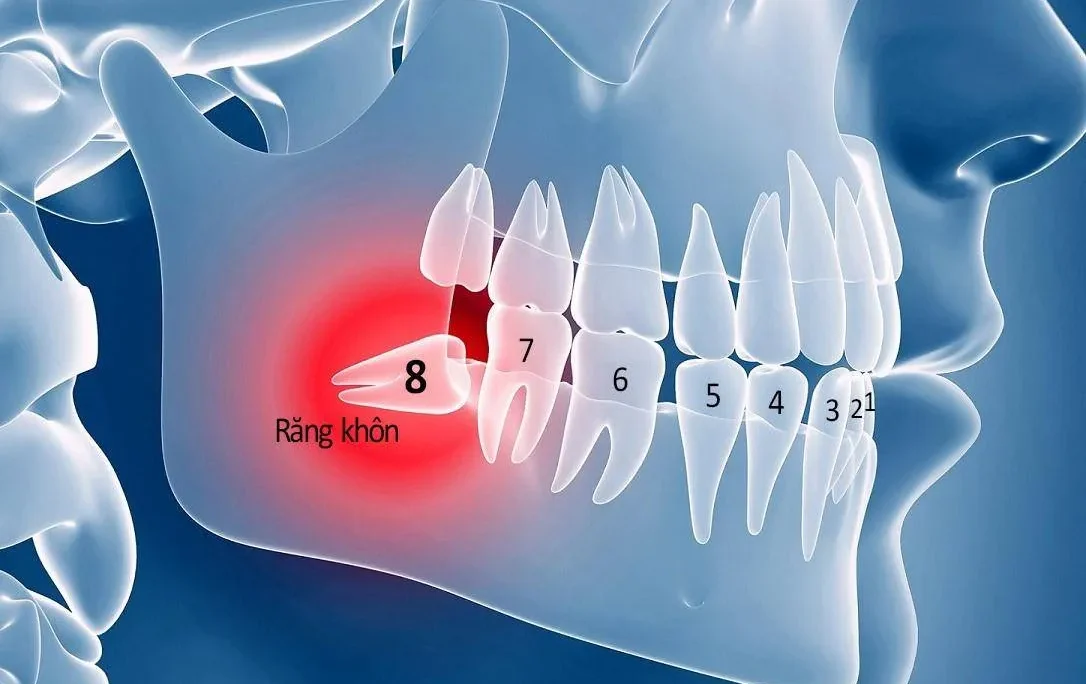

Để tối ưu hóa kết quả điều chỉnh nụ cười tại Hải Phòng, các nha khoa uy tín thường kết hợp thêm nhiều kỹ thuật hỗ trợ nhằm mang lại tính thẩm mỹ và chức năng tốt nhất. Với những trường hợp răng chỉ xỉn màu nhẹ, tẩy trắng răng công nghệ cao là giải pháp nhanh chóng và hiệu quả để cải thiện màu sắc tổng thể của nụ cười. Trám răng thẩm mỹ bằng Composite được ứng dụng để đóng các kẽ thưa nhỏ hoặc phục hồi những phần răng sứt mẻ nhẹ, giúp hàm răng đều và tự nhiên hơn mà không cần can thiệp quá sâu. Trong trường hợp thiếu răng, cấy ghép Implant được thực hiện nhằm phục hồi răng mất và đảm bảo sự đầy đủ trên cung hàm trước khi bước vào các giai đoạn thẩm mỹ tiếp theo. Sự kết hợp linh hoạt, đúng kỹ thuật và được thực hiện bởi đội ngũ chuyên môn cao chính là chìa khóa để kiến tạo một nụ cười vừa đẹp, vừa khỏe mạnh theo thời gian.